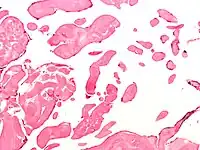

Micrograph of an excised aortic valve papillary fibroelastoma showing that the avascular branching papillae are covered by endothelium. H&E stain.

Papillary fibroelastoma are typically found and accurately diagnosed by imaging. The diagnosis is confirmed by pathology. Histologically, papillary fibroelastomas have branching avascular papillae, composed of collagen, that are covered by endothelium.